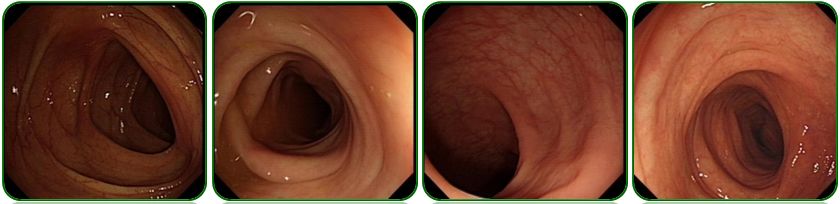

腹部CT提示腹盆腔中量积液,初步考虑结核可能,如图2;

图2 腹部CT检查

胃镜、肠镜未见异常,如图6;

图6 胃镜、肠镜检查